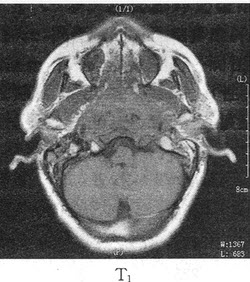

�����У�74�ꡣ��������������4���£�MRͼ�����£����п��ܵ�����ǣ���

A.ǰ��������

B.ǰ���ٰ�

C.ǰ��������

D.���װ�

E.����ǰ������